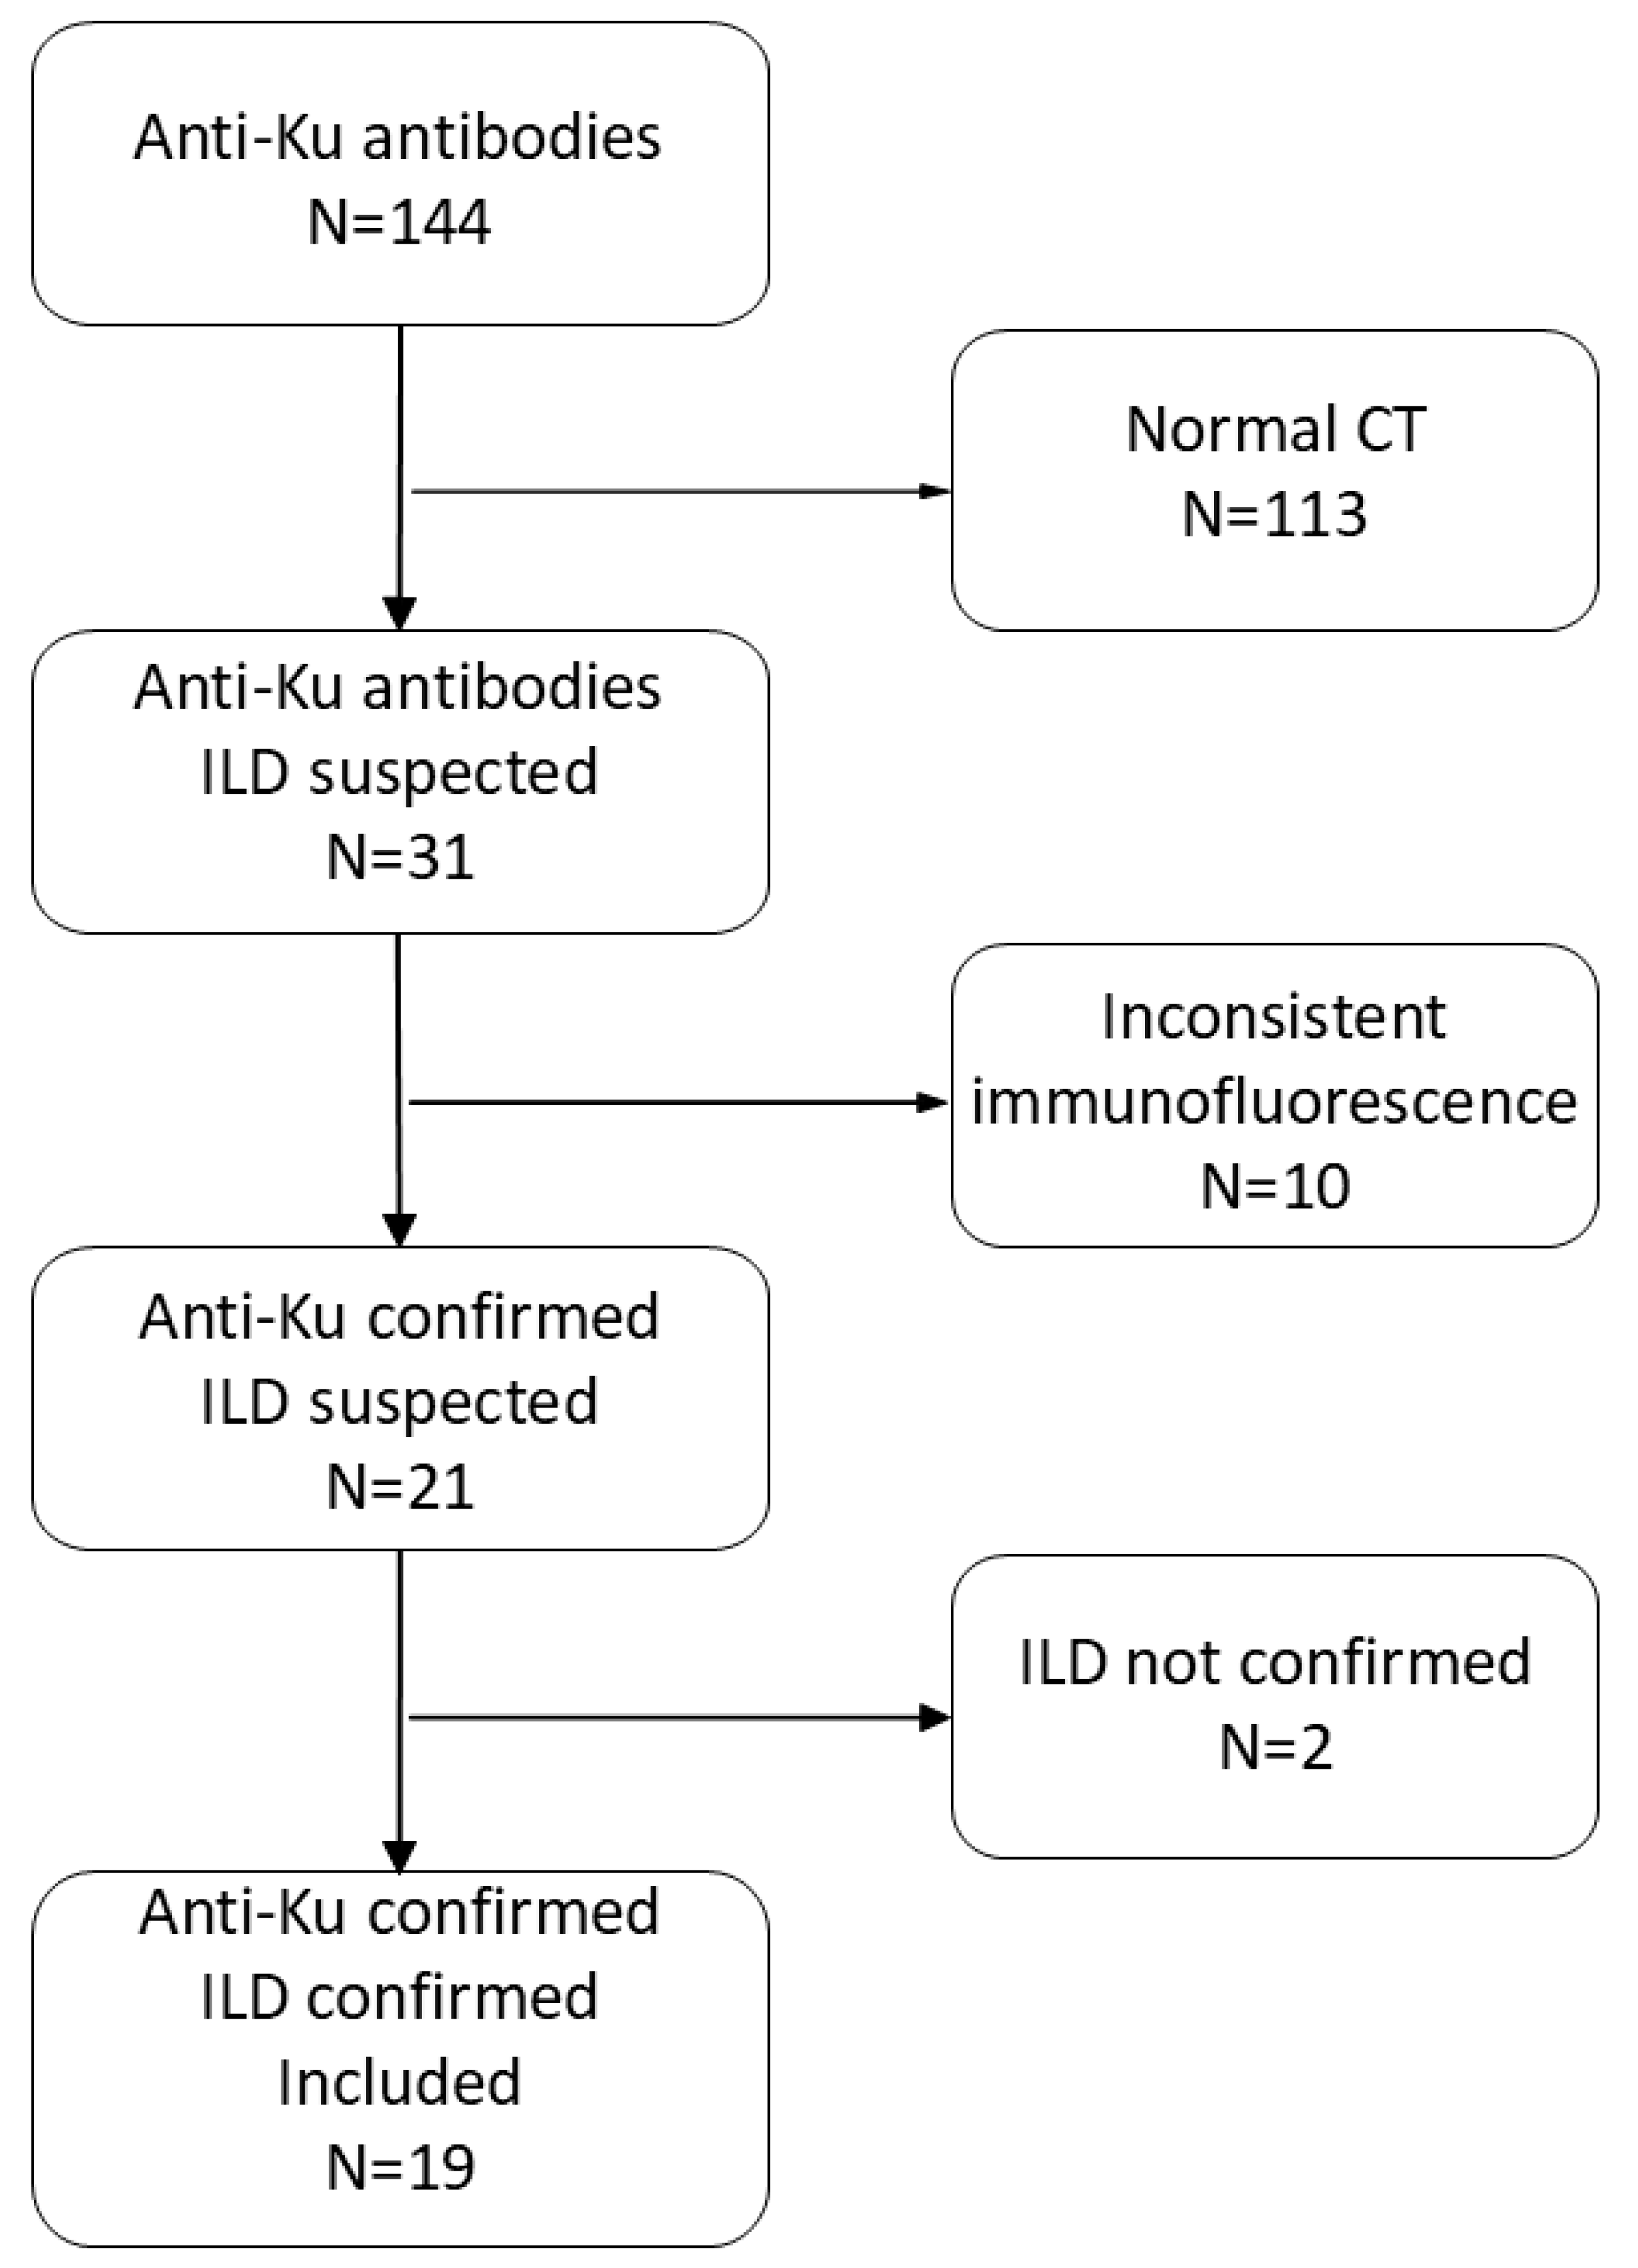

2.1. Study Design and Eligibility Criteria

3.1. Study Population